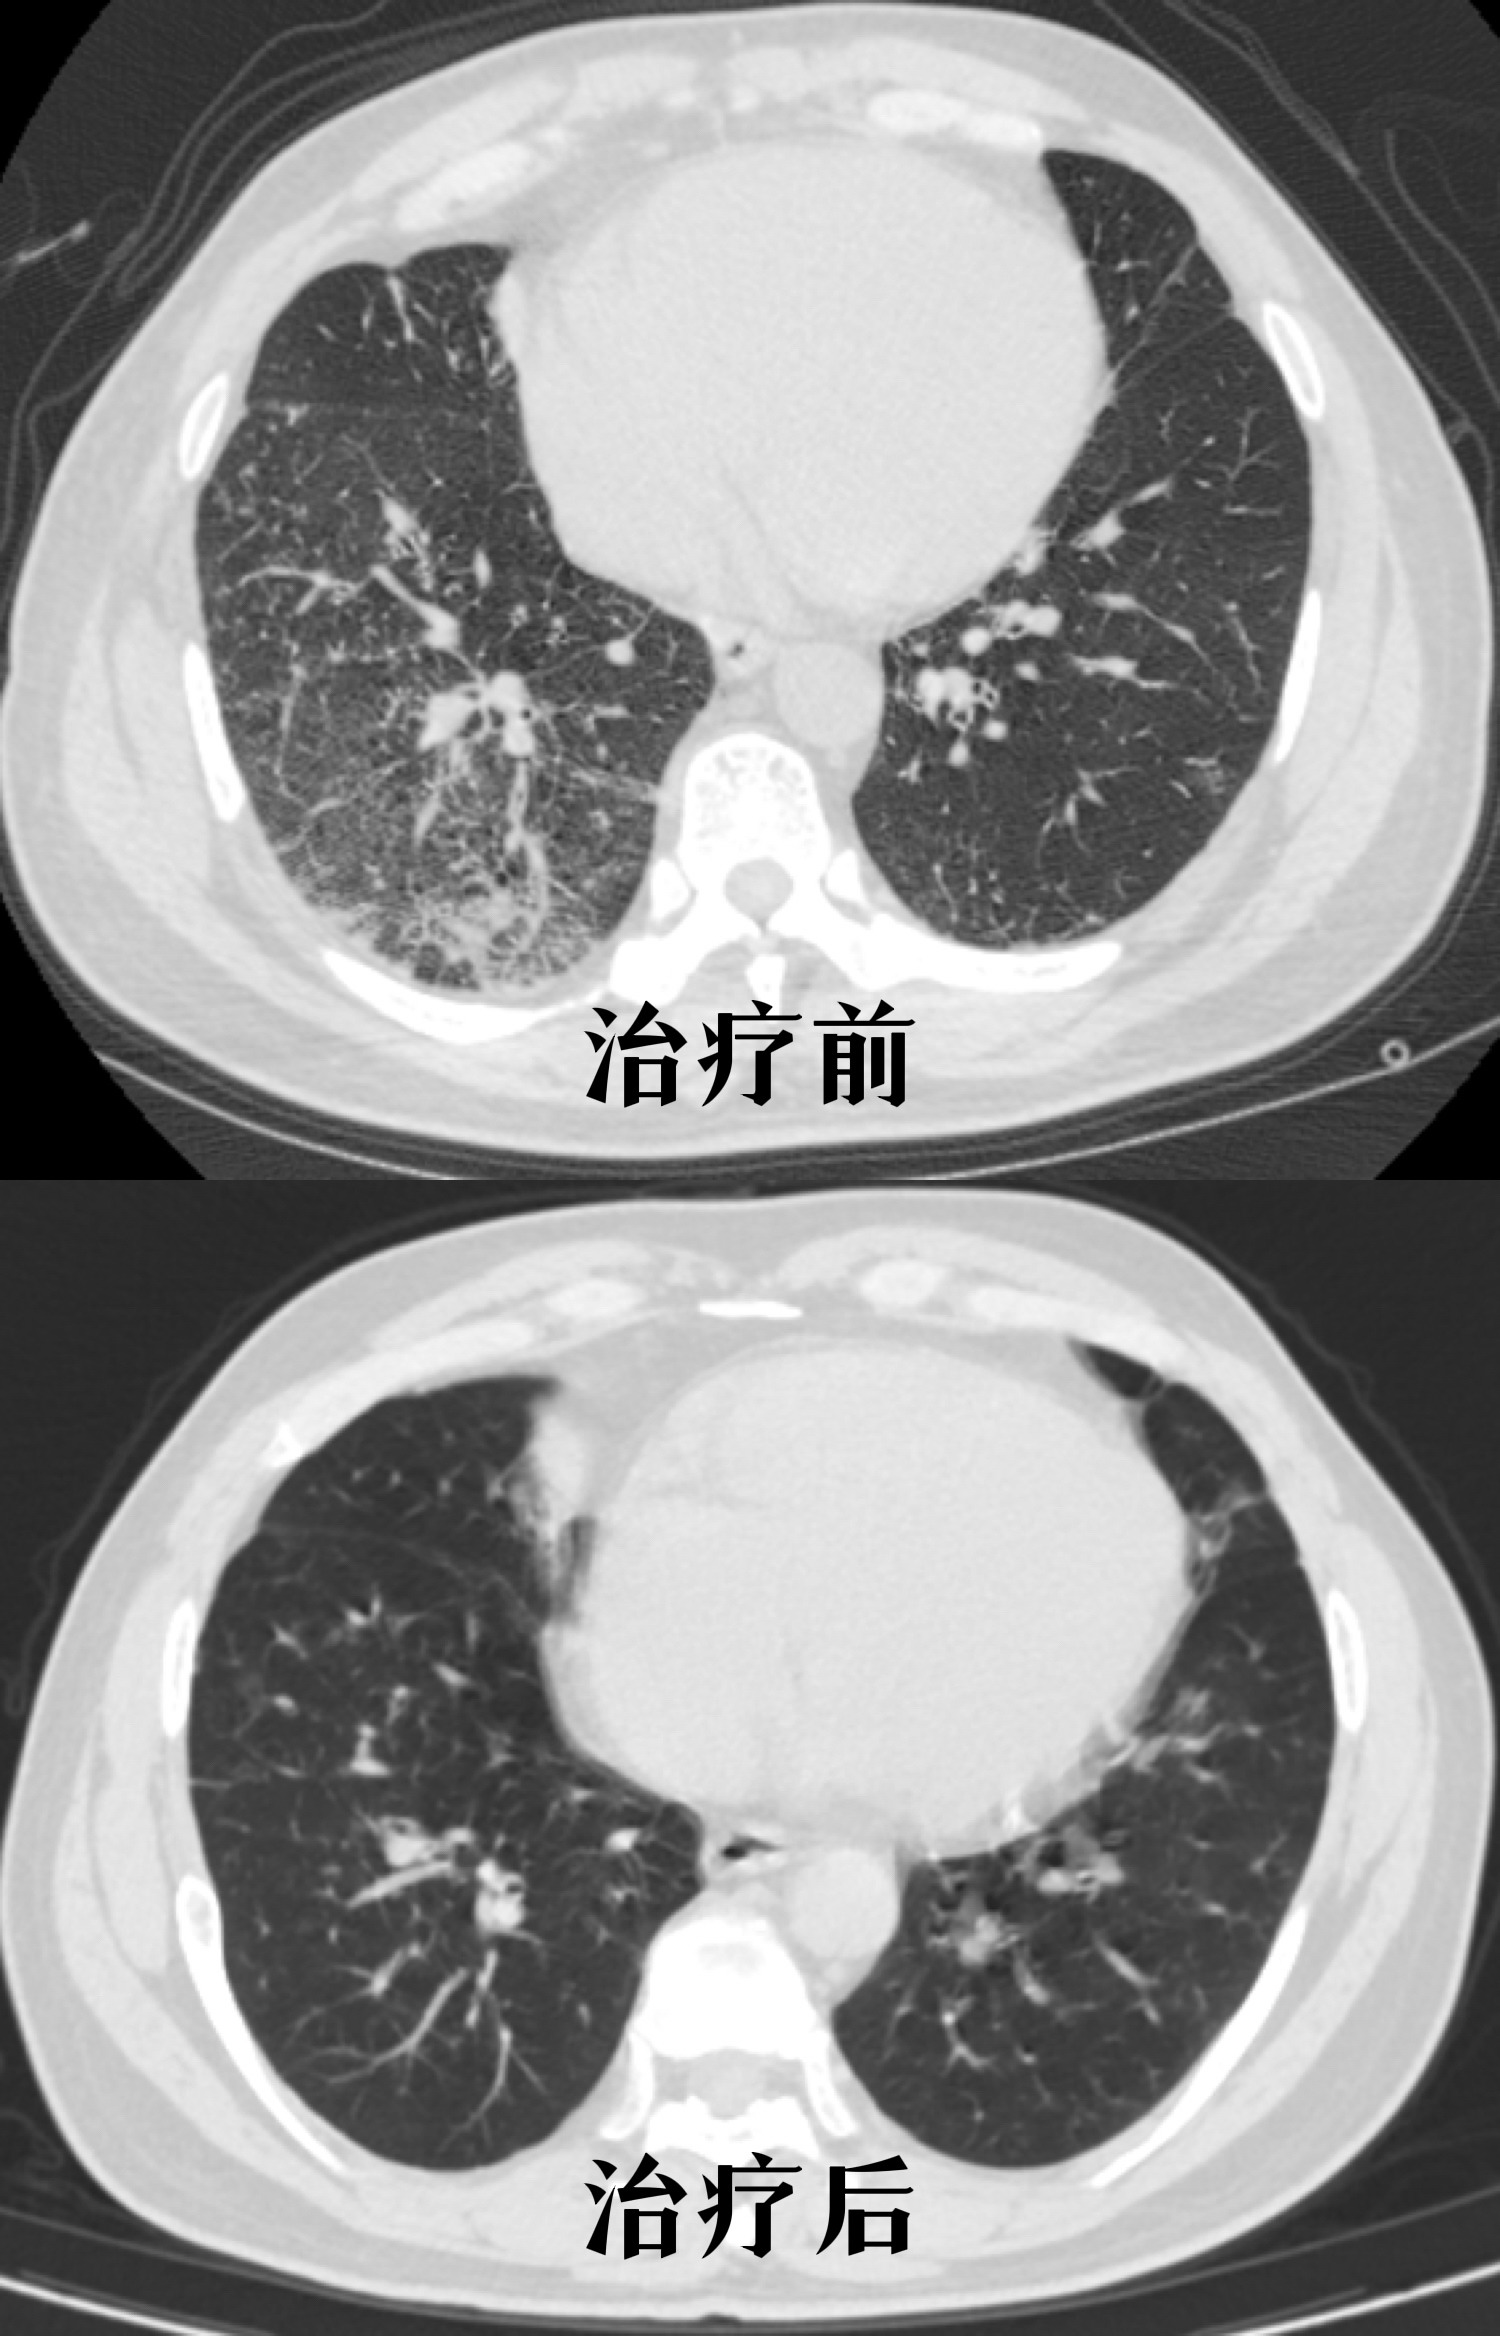

57岁女性细菌性肺炎致咳嗽,发热,药物治疗后症状消失